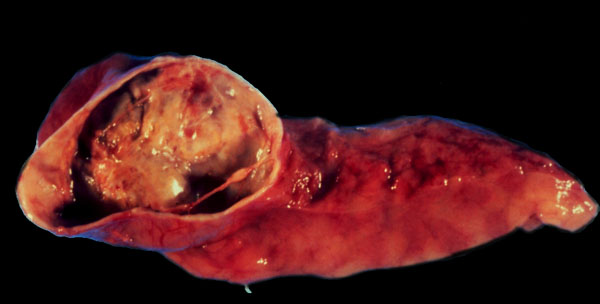

Pancreatic pseudocyst, gross.

Pseudocyst, gross. A pancreatic pseudocyst arising from the head of the pancreas. Pseudocysts are the result of chronic pancreatitis. The liquified tissue within may become seeded with bacteria, and transform into an abscess.